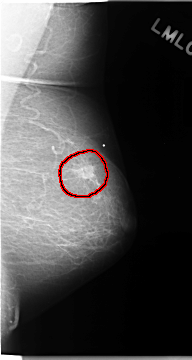

C_0118_1.RIGHT_MLO

FILE: C_0118_1.LEFT_MLO.OVERLAY

TOTAL_ABNORMALITIES 1

ABNORMALITY 1

LESION_TYPE MASS SHAPE IRREGULAR MARGINS ILL_DEFINED

ASSESSMENT 5

SUBTLETY 5

PATHOLOGY MALIGNANT

TOTAL_OUTLINES 1

BOUNDARY